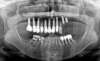

Panorex initial

Panorex de controle

Panorex et plan de traitement pour les secteurs postérieurs maxillaires et mandibulaires

Contrôle radio